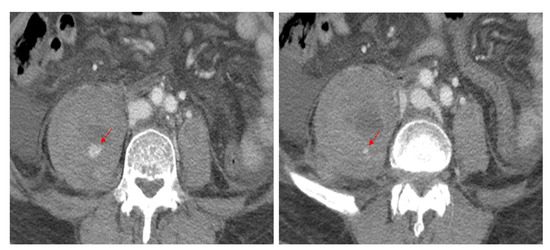

Figure 1.

Contrast-enhanced CT scans reveal high attenuation, indicating active bleeding (arrows) from the right second and third lumbar arteries within the hematoma.